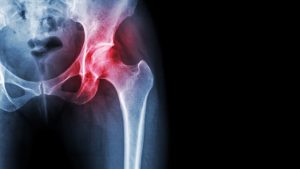

Causes of Hip Arthritis

The most common cause of chronic hip pain and disability is arthritis. The pain and lack of motion associated with hip arthritis can present as knee pain and worsen back pain due to altered body mechanics.

- Osteoarthritis – This is an age-related “wear and tear” type of arthritis. It usually occurs in people 50 years of age and older and often in individuals with a family history of arthritis. The cartilage cushioning the bones of the hip wears away. The bones then rub against each other, causing hip pain and stiffness. Osteoarthritis may also be caused or accelerated by subtle irregularities in how the hip developed in childhood.

- Rheumatoid arthritis – This is an autoimmune disease in which the synovial membrane becomes inflamed and thickened. This chronic inflammation can damage the cartilage, leading to pain and stiffness. Rheumatoid arthritis is the most common type of a group of disorders termed “inflammatory arthritis.”

- Post-traumatic arthritis – This can follow a serious hip injury or fracture. The cartilage may become damaged and lead to hip pain and stiffness over time.

- Avascular necrosis – An injury to the hip, such as a dislocation or fracture, may limit the blood supply to the femoral head. This is called avascular necrosis (also commonly referred to as “osteonecrosis”). The lack of blood may cause the surface of the bone to collapse, and arthritis will result. Some diseases can also cause avascular necrosis.

- Childhood hip disease – Some infants and children have hip problems. Even though the problems are successfully treated during childhood, they may still cause arthritis later on in life. This happens because the hip may not grow normally, and the joint surfaces are affected.